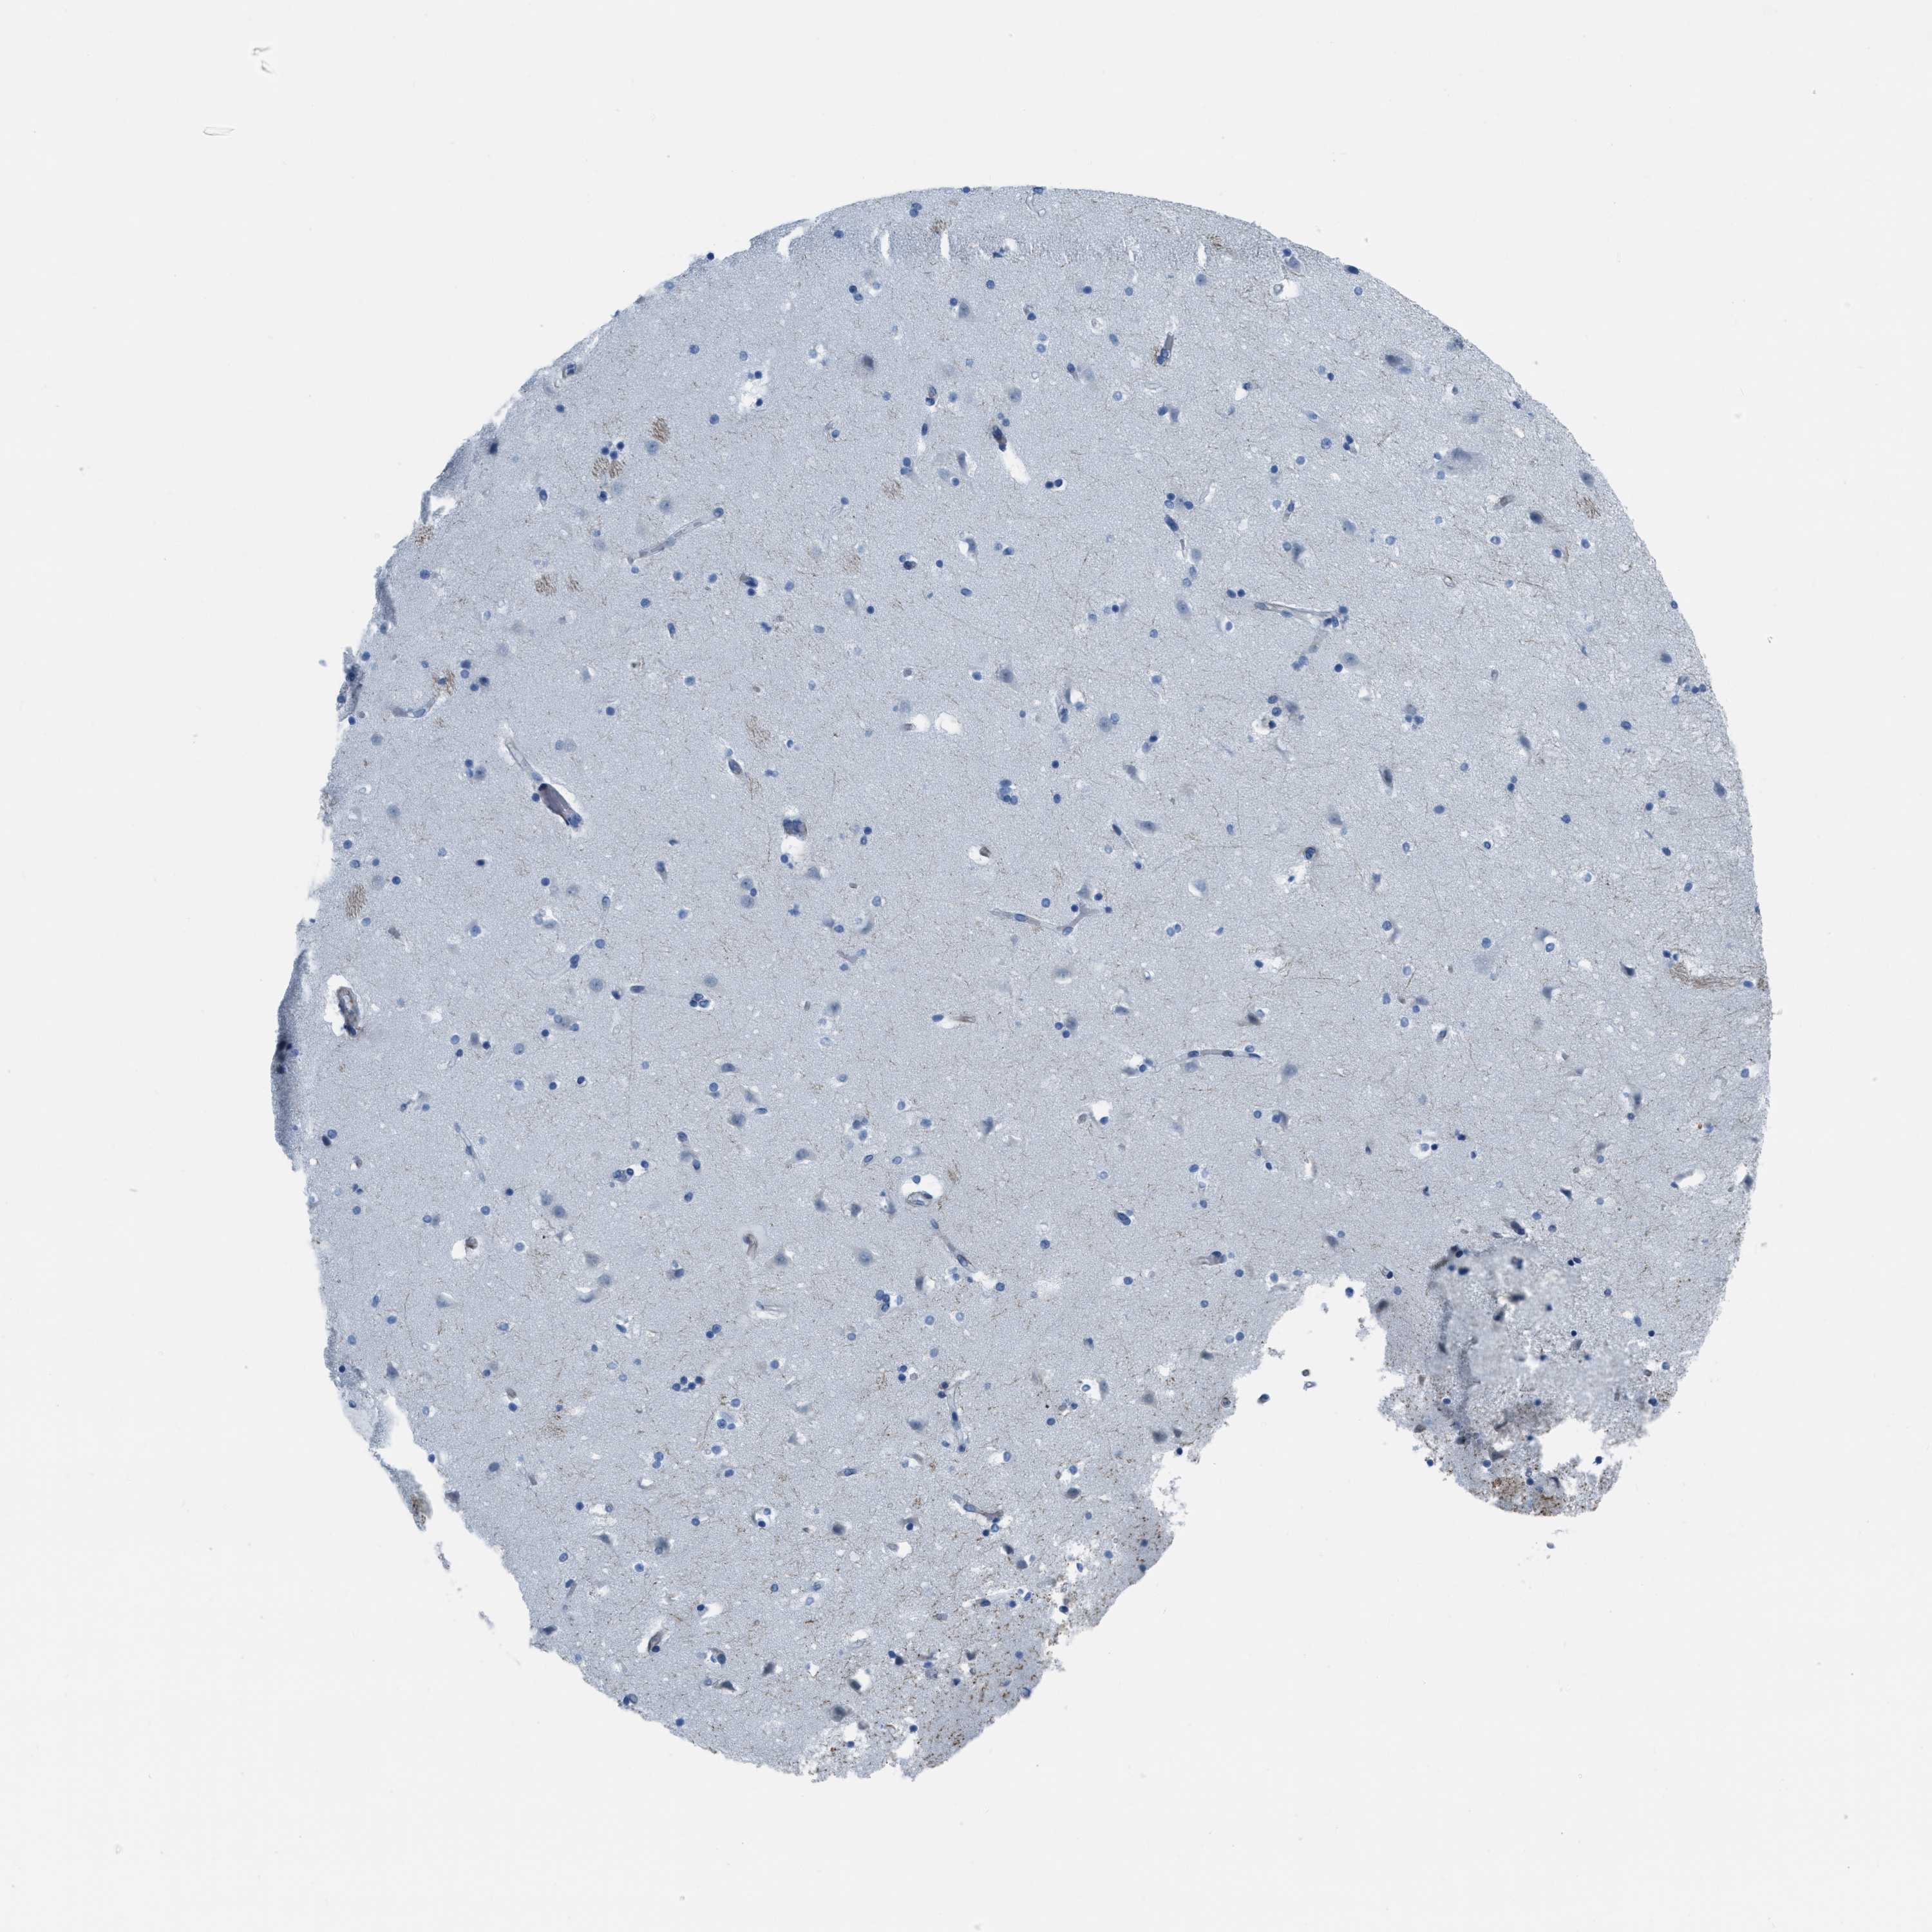

CAUDATE - Antibody stainingi

Antibody staining in the annotated cell types in the current human tissue is reported as not detected, low, medium, or high, based on conventional immunohistochemistry profiling in selected tissues. This score is based on the combination of the staining intensity and fraction of stained cells.

Each image is clickable and will lead to virtual microscopy that enables deeper exploration of all samples and also displays staining intensity scores, fraction scores and subcellular localization as well as patient and tissue information for each sample.

Antibody HPA014967Antibody HPA018107

Glial cells Not detectedNot detected

Neuronal cells Not detectedNot detected